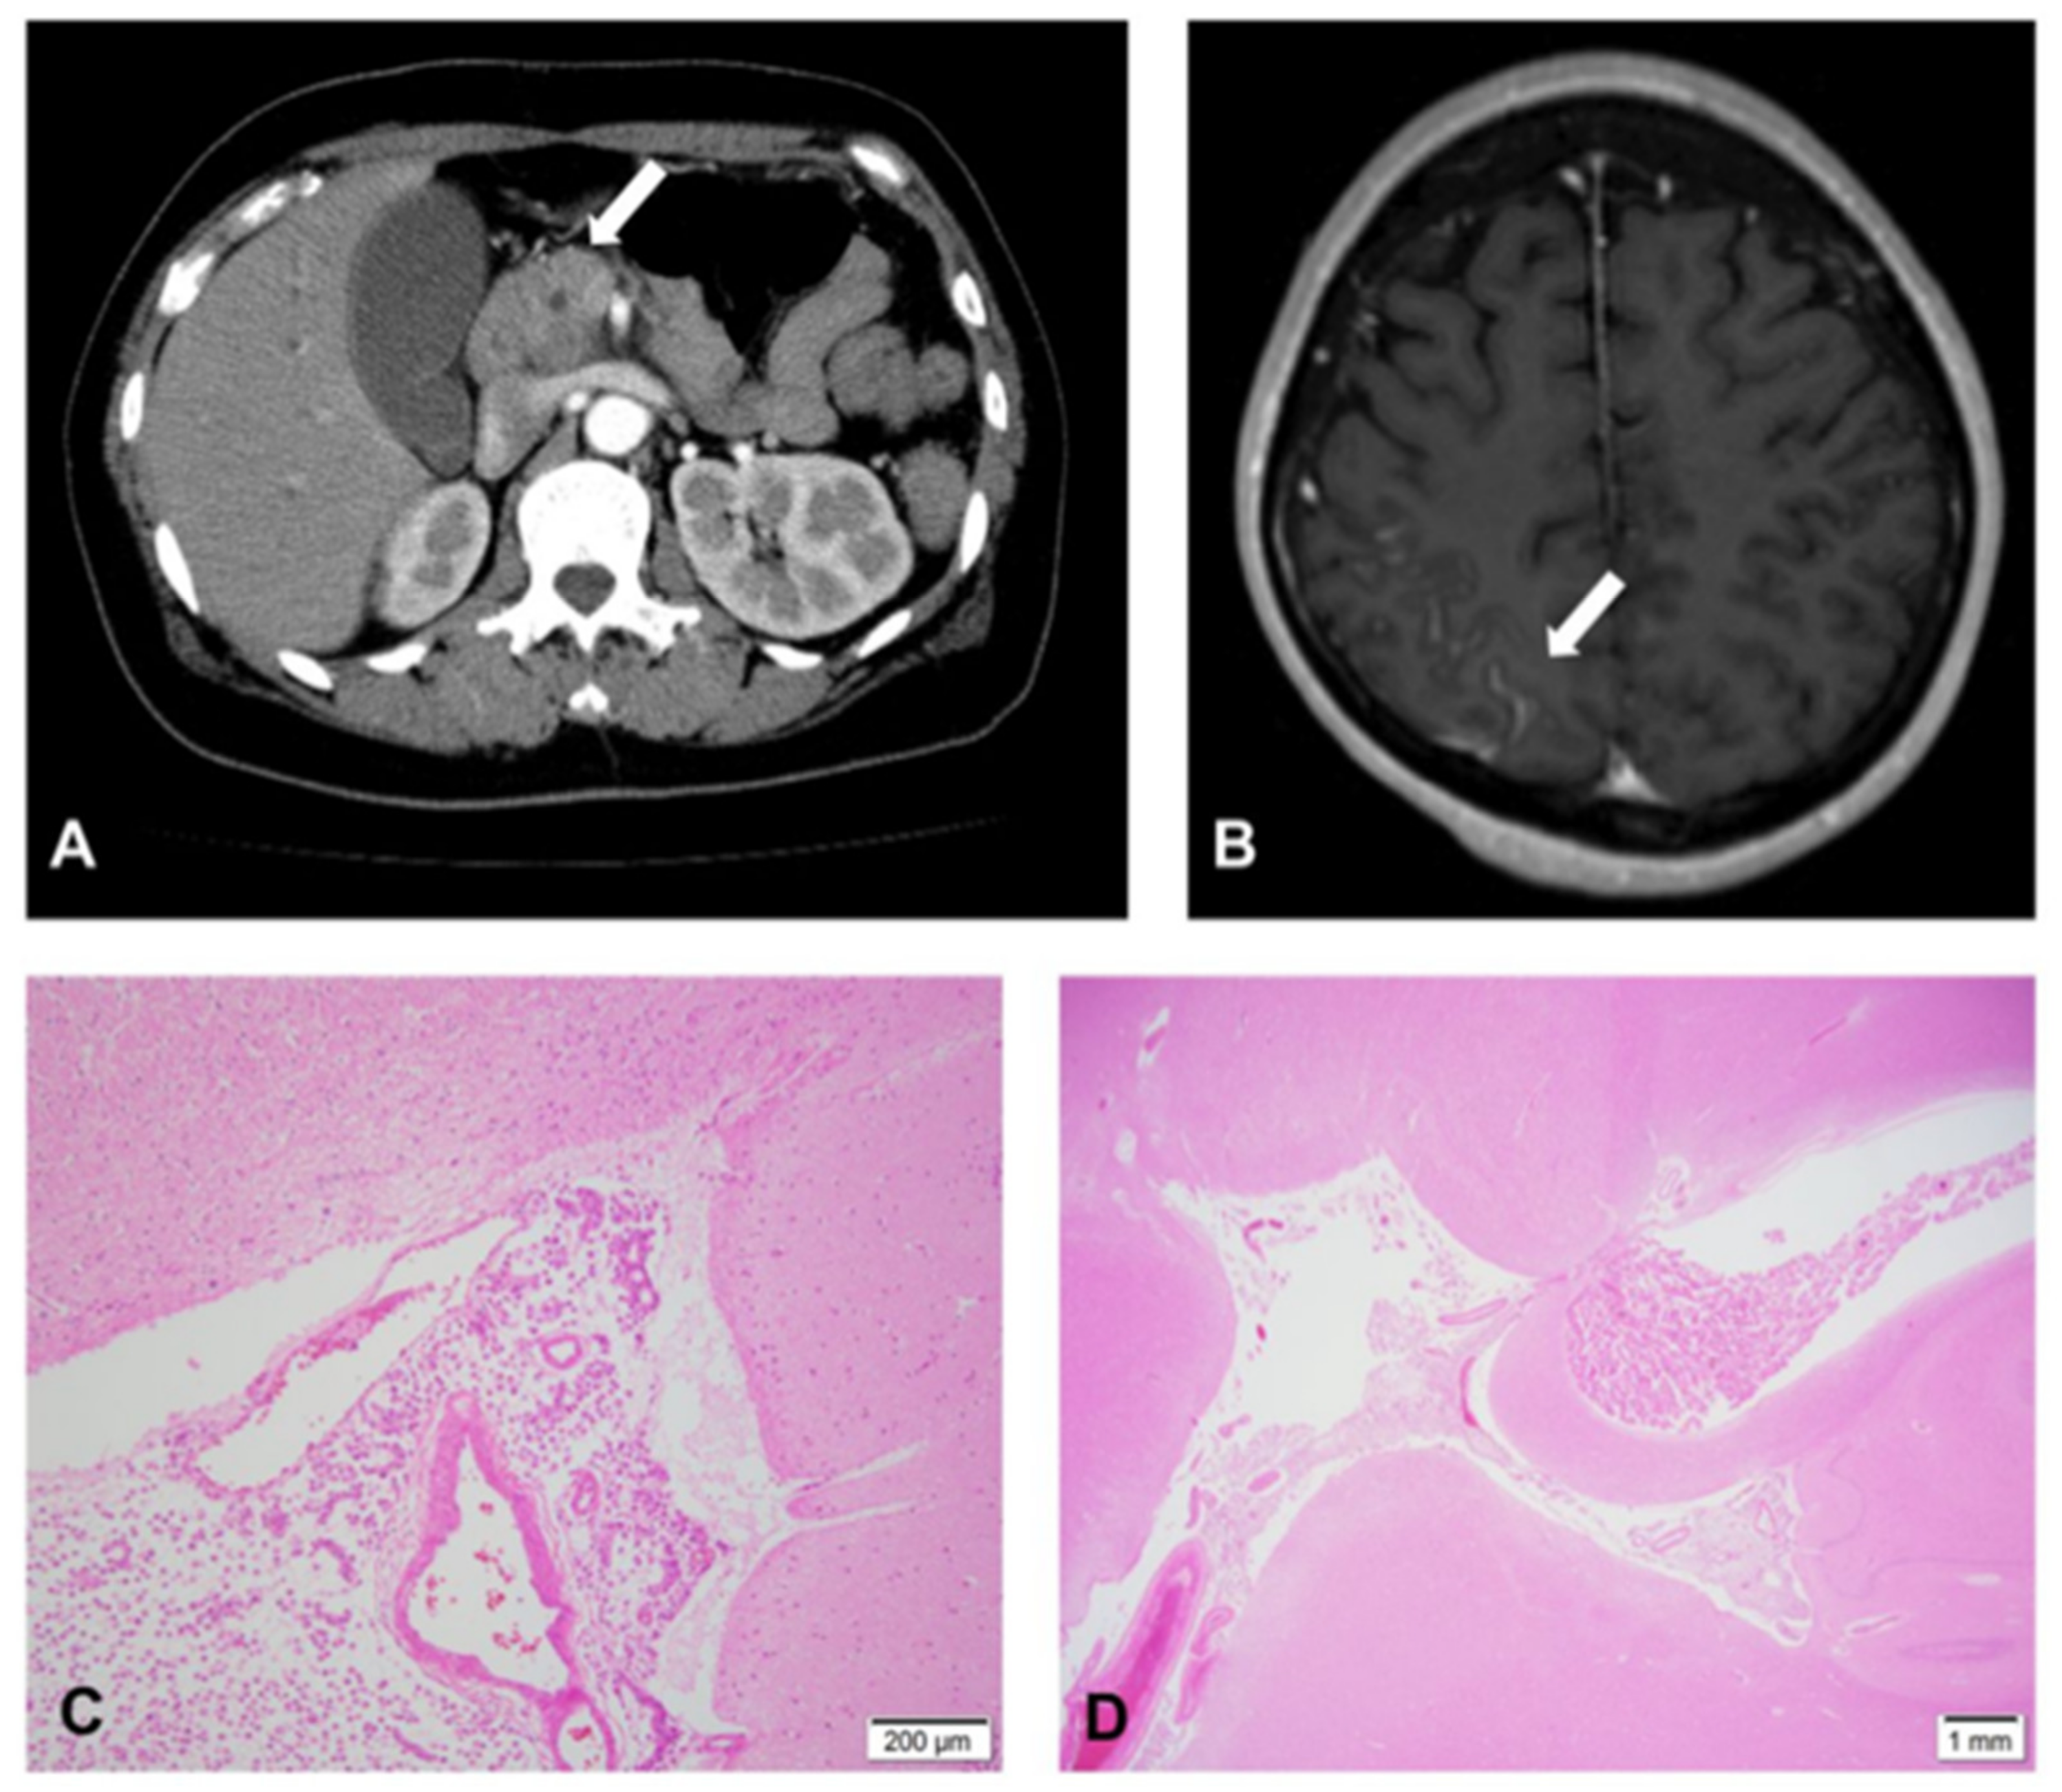

2. Case Report